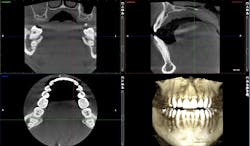

The new digital approach (figures 2–13) to an osseous crown lengthening procedure involves photographs, radiographs, intraoral scans, and CBCT data for a facially driven treatment plan. This approach starts with the end result in mind and ultimately requires fewer appointments for the patient. It also leads to more predictable esthetic results.

Utilizing a facially driven treatment plan, the facial photographs were merged with the CBCT scan to assess bone levels, and the central incisors were digitally planned to exhibit a new length of 11.5 mm, to enhance the patient’s long facial structure. The new width of the veneers could then be generated to be 85% of this measurement to achieve the golden proportion for optimal esthetics. Once the surgical guide is designed in Exocad to achieve these coronal margins, the guide design is exported to SprintRay to be printed with a snug fit for accurate coronal margination for the final restorations later on.